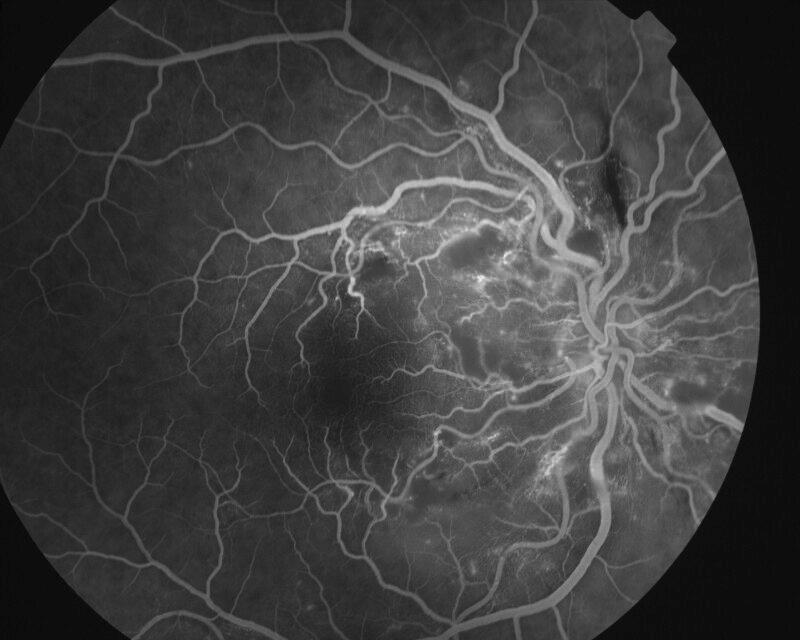

RETINOPATHIE HYPERTENSIVE

IM000018.jpg